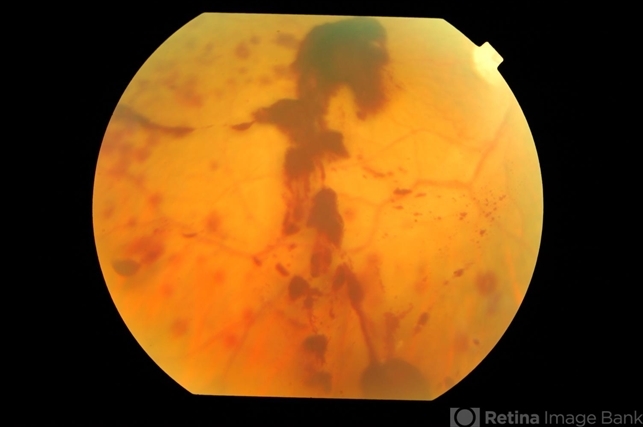

- anaemic retinopathy, vitreous hemorrhage

- Vitreous haemorrhage in a 25-year-old gentleman with severe anaemia and thrombocytopenia.